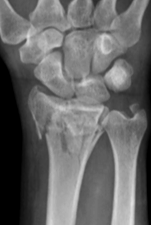

• Elbow, wrist and carpus fractures, mal-unions or non-unions

• Osteoarthritis